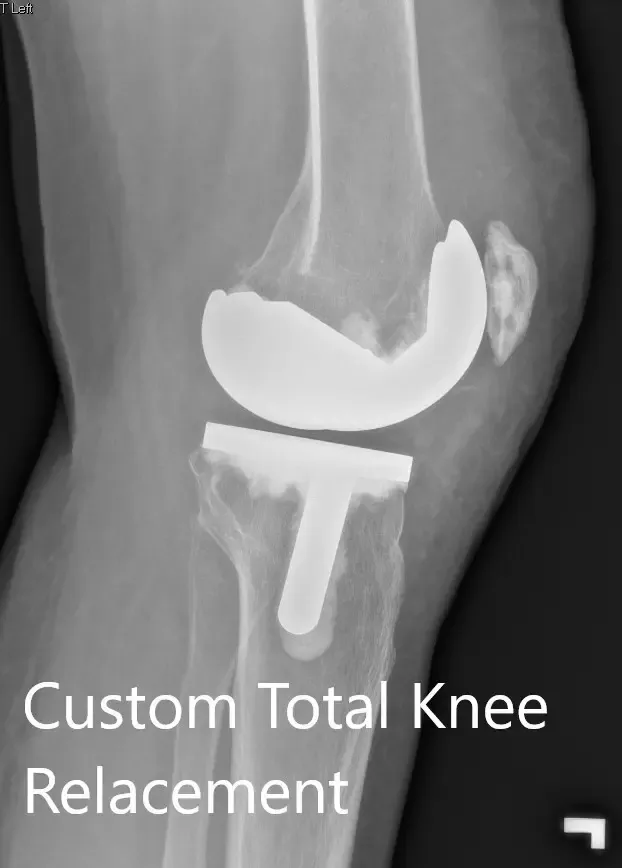

Radiografía postoperatoria que muestra la vista lateral de la rodilla derecha e izquierda, respectivamente